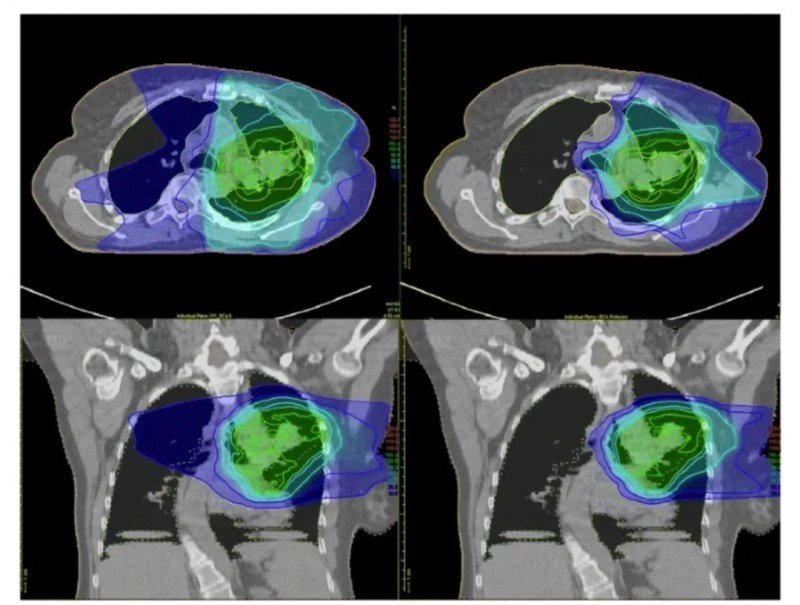

下图以局部晚期非小细胞肺癌(NSCLC)患者为例,对比了调强放射治疗(IMRT,左图)与质子治疗(右图)的辐射剂量分布:传统放疗会将辐射传递至肿瘤及周围大片健康组织,而质子治疗可将绝大部分辐射集中于肿瘤区域,对危及器官(OAR)的辐射剂量显著更低。

▲图源“BMC”,版权归原作者所有,如无意中侵犯了知识产权,请联系我们删除